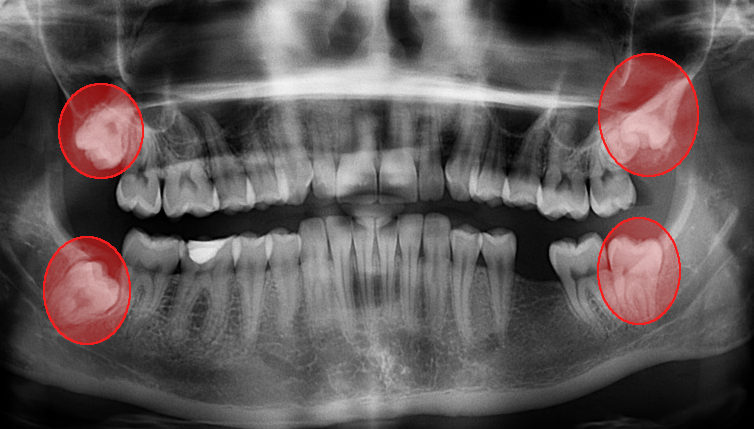

Pathologie de la dentition

Pathologie dento-maxillaire